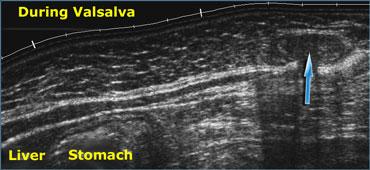

Siêu âm thời gian thực cho phép quan sát các tác động của nghiệm pháp Valsalva. Mỡ trong ổ bụng bị đẩy vào thành bụng (mũi tên) qua một thoát vị thượng vị.

- Khả năng hiển thị động, thời gian thực của siêu âm là đặc tính độc đáo không thể thay thế. Siêu âm có thể quan sát chuyển động của thai nhi, nhu động ruột và cả tình trạng mất nhu động như trong liệt ruột.

Siêu âm có thể trực tiếp hiển thị dòng chảy máu và nhịp đập mạch, đồng thời cũng có thể đánh giá các tác động của hô hấp, nghiệm pháp Valsalva, trọng lực và lực ép.